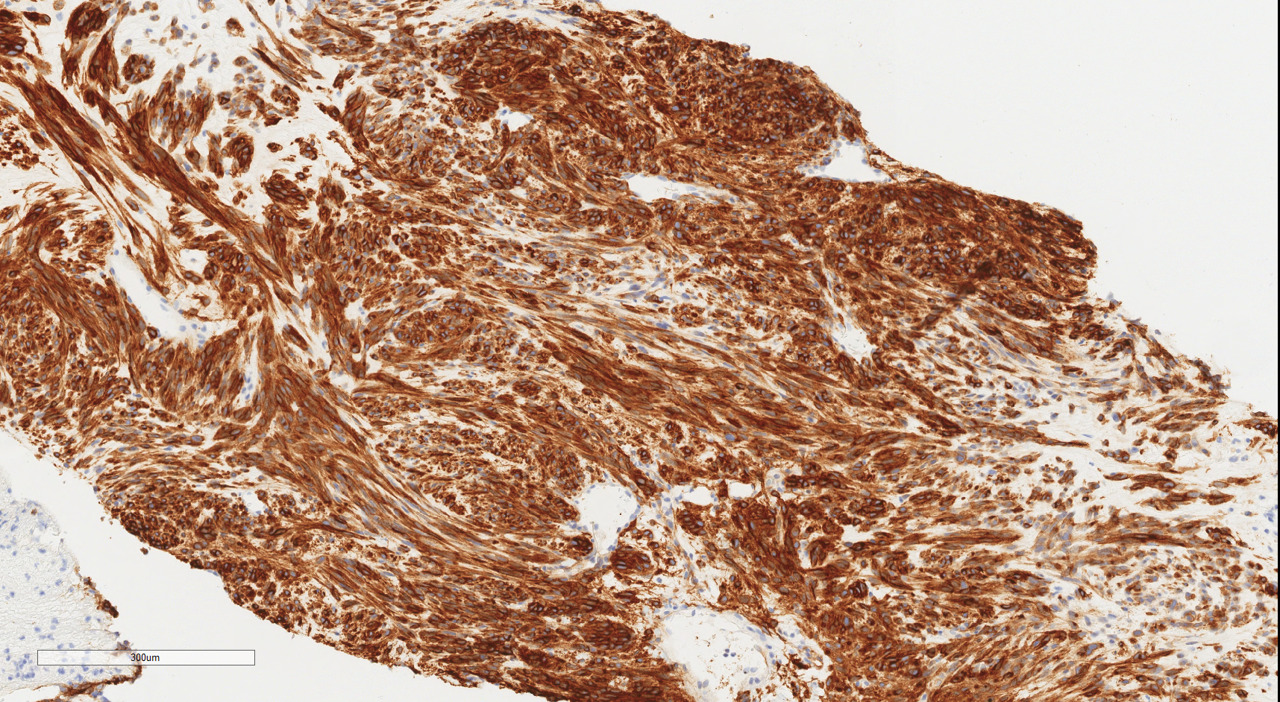

The patient was discharged home on postpartum day seven. At her surgical oncology appointment four weeks later, she continued to show signs of malnutrition with a weight loss of 20 kg compared to her intrapartum weight. An ultrasound-guided biopsy of her retroperitoneal mass confirmed the diagnosis of GIST with spindled morphology and multiple liver metastases (Figures 4 and 5). The patient’s case was reviewed in a multidisciplinary gastrointestinal tumor board, where neoadjuvant imatinib therapy was recommended. At her follow-up visit, the patient reported an increased appetite, and the size of her abdominal wall mass had decreased by approximately half. Due to an excellent initial response to imatinib therapy, this was to be continued with imaging at three-month intervals to assess her disease status; however, this plan was complicated by the SARS-CoV-2 pandemic, as the patient traveled oversees and was unable to return for several months. She did continue to take imatinib without difficulty during this time period.